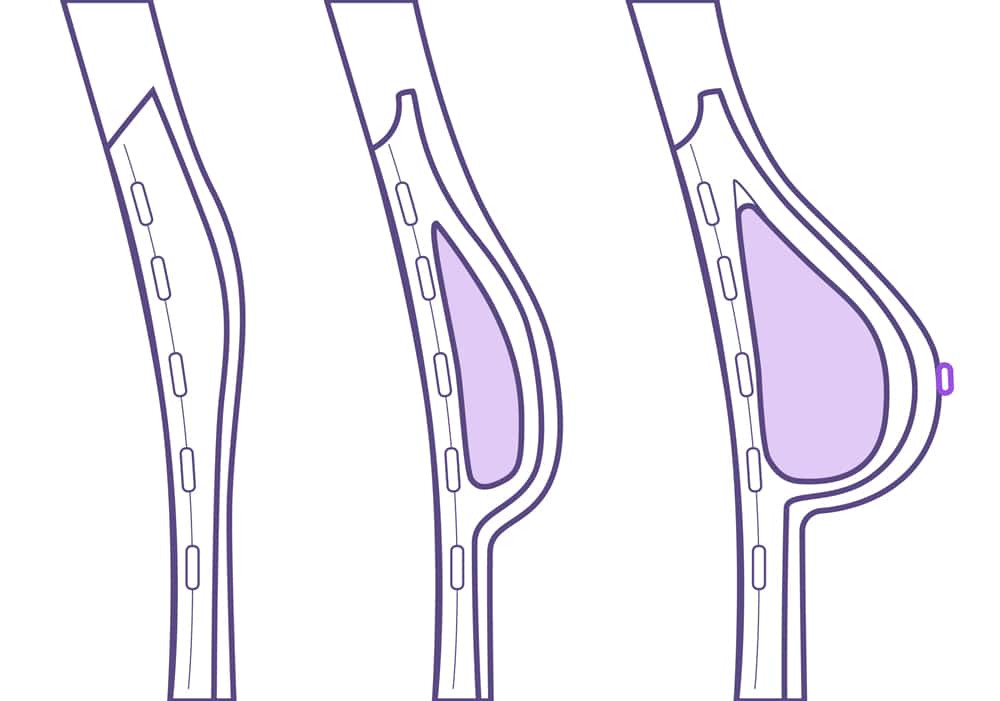

La técnica de la expansión cutánea es la más utilizada y consiste en expandir la piel para, posteriormente, colocar una prótesis. Después de la mastectomía, el cirujano plástico coloca un expansor debajo de la piel y músculo del pecho. A través de un mecanismo de válvula introduce una solución de suero salino una vez a la semana, durante varias semanas, hasta rellenar el expansor. Una vez que la piel se ha dado de sí lo suficiente, se retira este expansor y se sustituye por una prótesis mamaria de silicona.

La técnica de expansión cutánea implicará una segunda cirugía para la colocación del implante definitivo, pero en el caso de una reconstrucción inmediata se puede conseguir la colocación de la prótesis directamente sin pasar por todo el proceso de expansión.

Esto se puede lograr gracias a la implantación de una lámina especial que va a proteger a la prótesis sin necesidad de haber expandido la piel durante semanas. De esta forma, la paciente que entra en el quirófano para una mastectomía sale del mismo con su pecho totalmente reconstruido en la misma intervención.